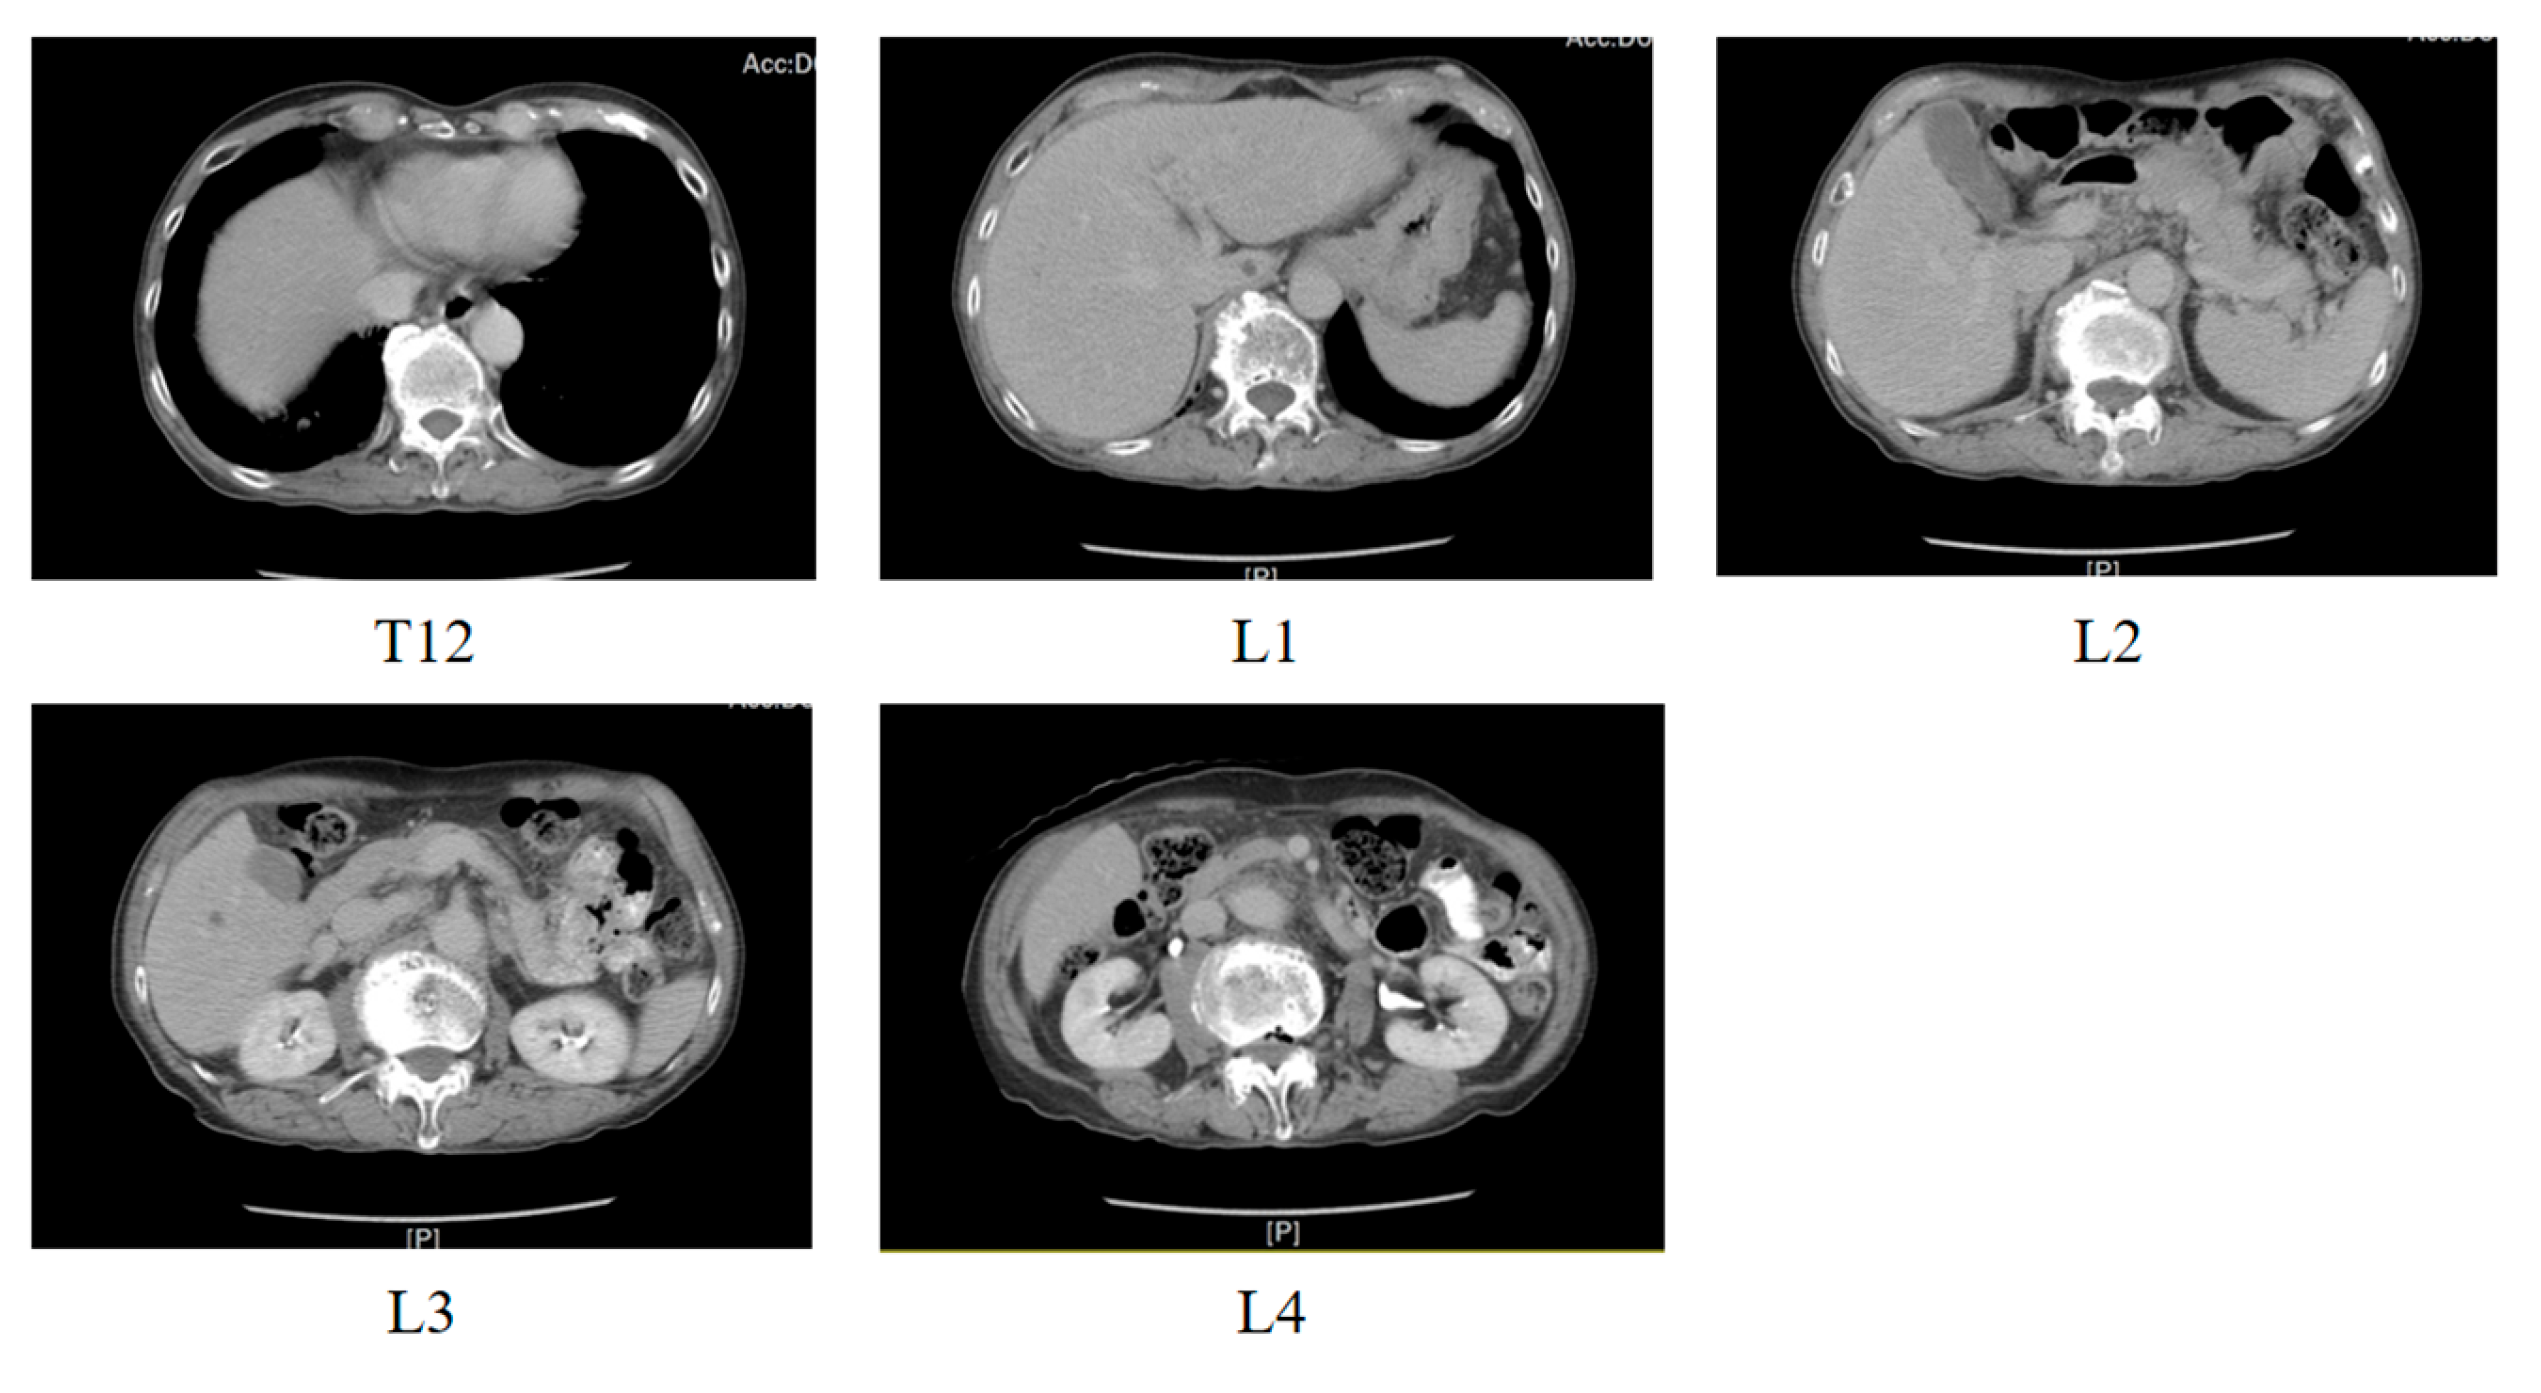

3.3.1. Dataset Description

3.3.2. Dataset Partitioning and Data Preprocessing

| All | T12 | L1 | L2 | L3 | L4 | |

|---|---|---|---|---|---|---|

| Number of Datasets | 2512 | 474 | 482 | 510 | 548 | 498 |

| Number of Patients | Number of Datasets | T12 | L1 | L2 | L3 | L4 | |

|---|---|---|---|---|---|---|---|

| Training dataset | 67 | 2003 | 383 | 380 | 408 | 441 | 391 |

| Testing dataset | 17 | 509 | 91 | 102 | 102 | 107 | 107 |